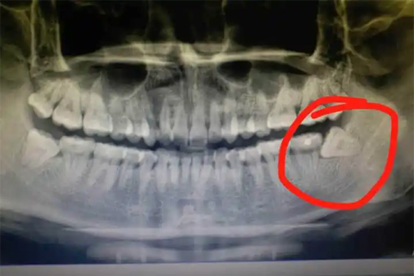

术后3-5天出现的剧烈疼痛可能为干槽症,因血凝块脱落导致骨面暴露引发。疼痛常放射至耳颞部,伴腐臭味。需及时清创并使用盐酸利多卡因注射液局部麻醉,配合复方氯己定含漱液保持口腔清洁。